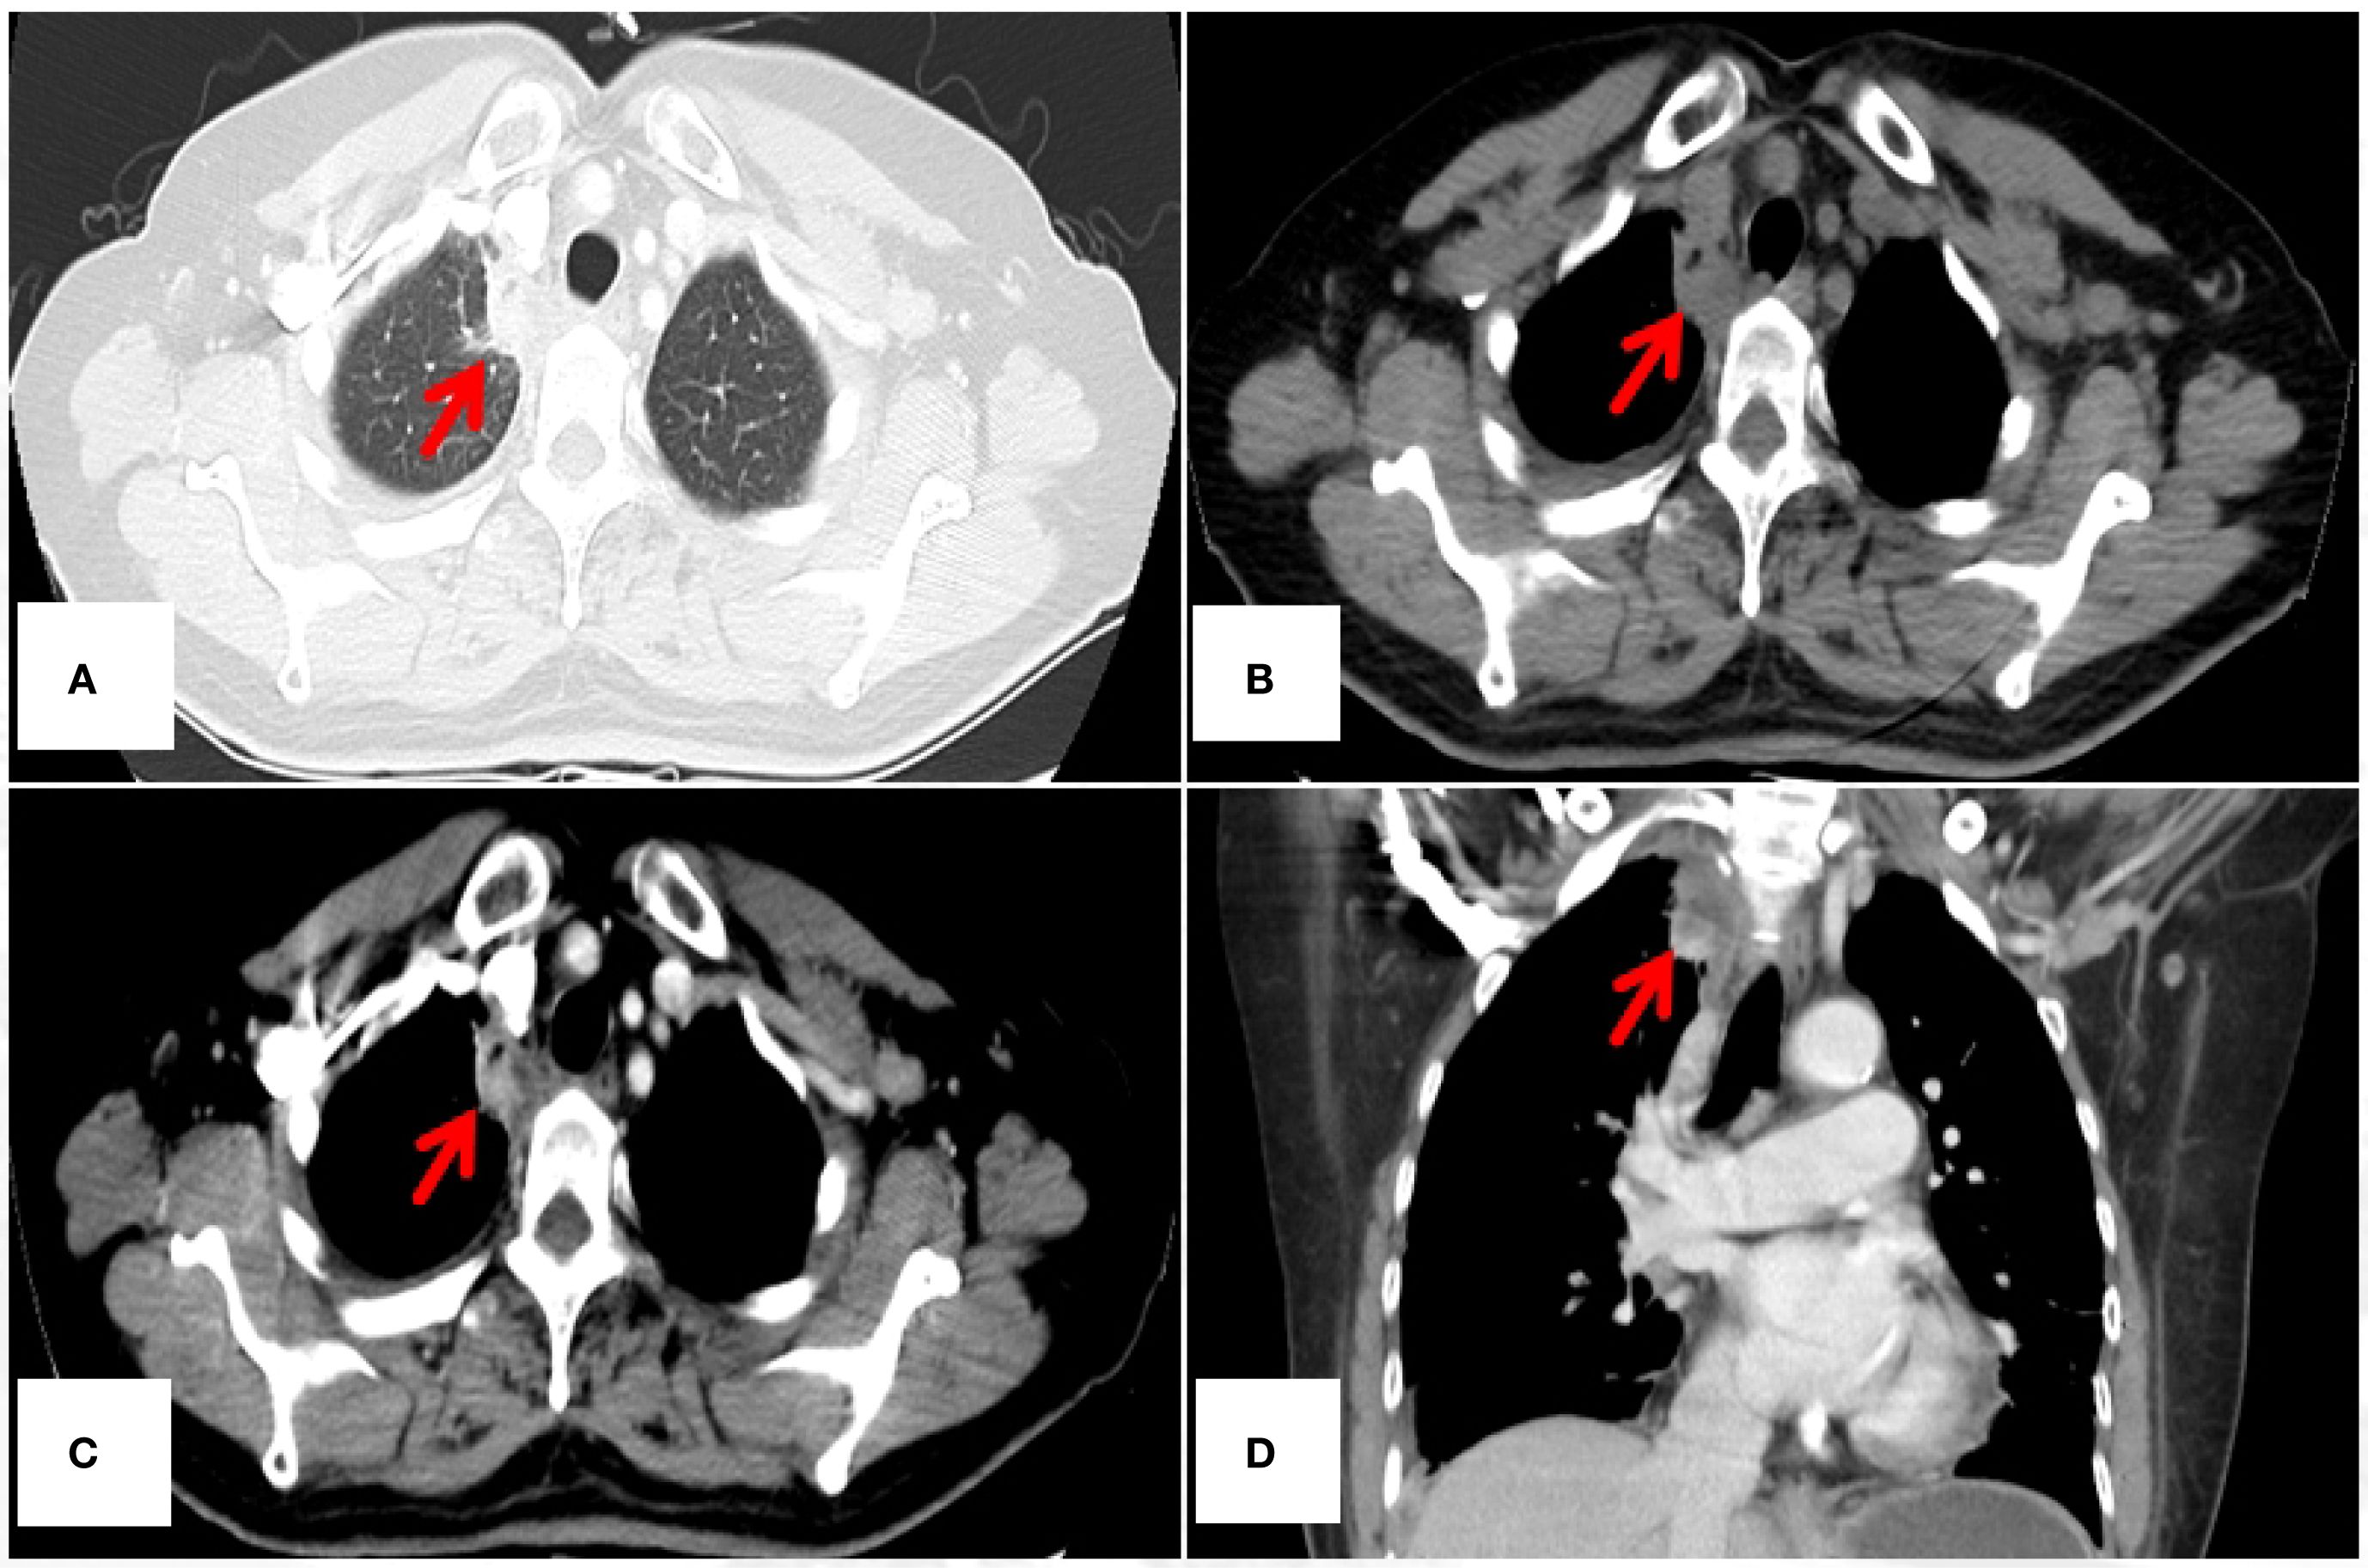

The authors used only non-contrast-enhanced CT (NCECT) for postoperative surveillance from July 2021 to March 2024. Of particular concern is that, for malignant lesions demonstrating “heterogeneous enhancement” on contrast-enhanced CT (CECT) as documented in this ETAC case, the inherent limitations of NCECT in soft tissue characterization may substantially reduce diagnostic specificity. Take a case of ETAC in our center as an example (see Figures 1A-D). The vascular heterogeneity and necrotic components characteristic of malignant tumors produce distinctive enhancement patterns on CECT, whereas both postoperative changes (e.g., fibrotic remodeling, atelectasis) and inflammatory processes manifest as isodense shadows on NCECT. This makes it challenging to differentiate tumor recurrence from benign structural alterations. Current evidence from multiple studies demonstrates the superior diagnostic performance of CECT in detecting locoregional recurrences (including hilar, mediastinal, and pleural recurrences) during postoperative surveillance of pulmonary malignancies (2–4). In the present case, exclusive reliance on NCECT for assessing disease progression (August 2023) and monitoring response to PD-1 inhibitor therapy (October 2023 and March 2024) may preclude accurate characterization of soft tissue density biology (viable tumor versus scar tissue versus inflammatory changes), potentially confounding the objective interpretation of therapeutic outcomes.

Figure 1. 45-year-old female diagnosed with ETAC. Immunocytochemistry shows: Ber - EP4(+), CK7(+), TTF - 1(SPT24)(-), Napsin A(-), Villin(+), CDX - 2(+), GATA3(-), PAX8(-), CR(-). (A) Lesion under lung window (arrow); (B) Lesion under mediastinal window non – contrast (arrow), (C, D) Lesion under mediastinal window contrast - enhanced, showing heterogeneous enhancement(arrow). CT, computed tomography.